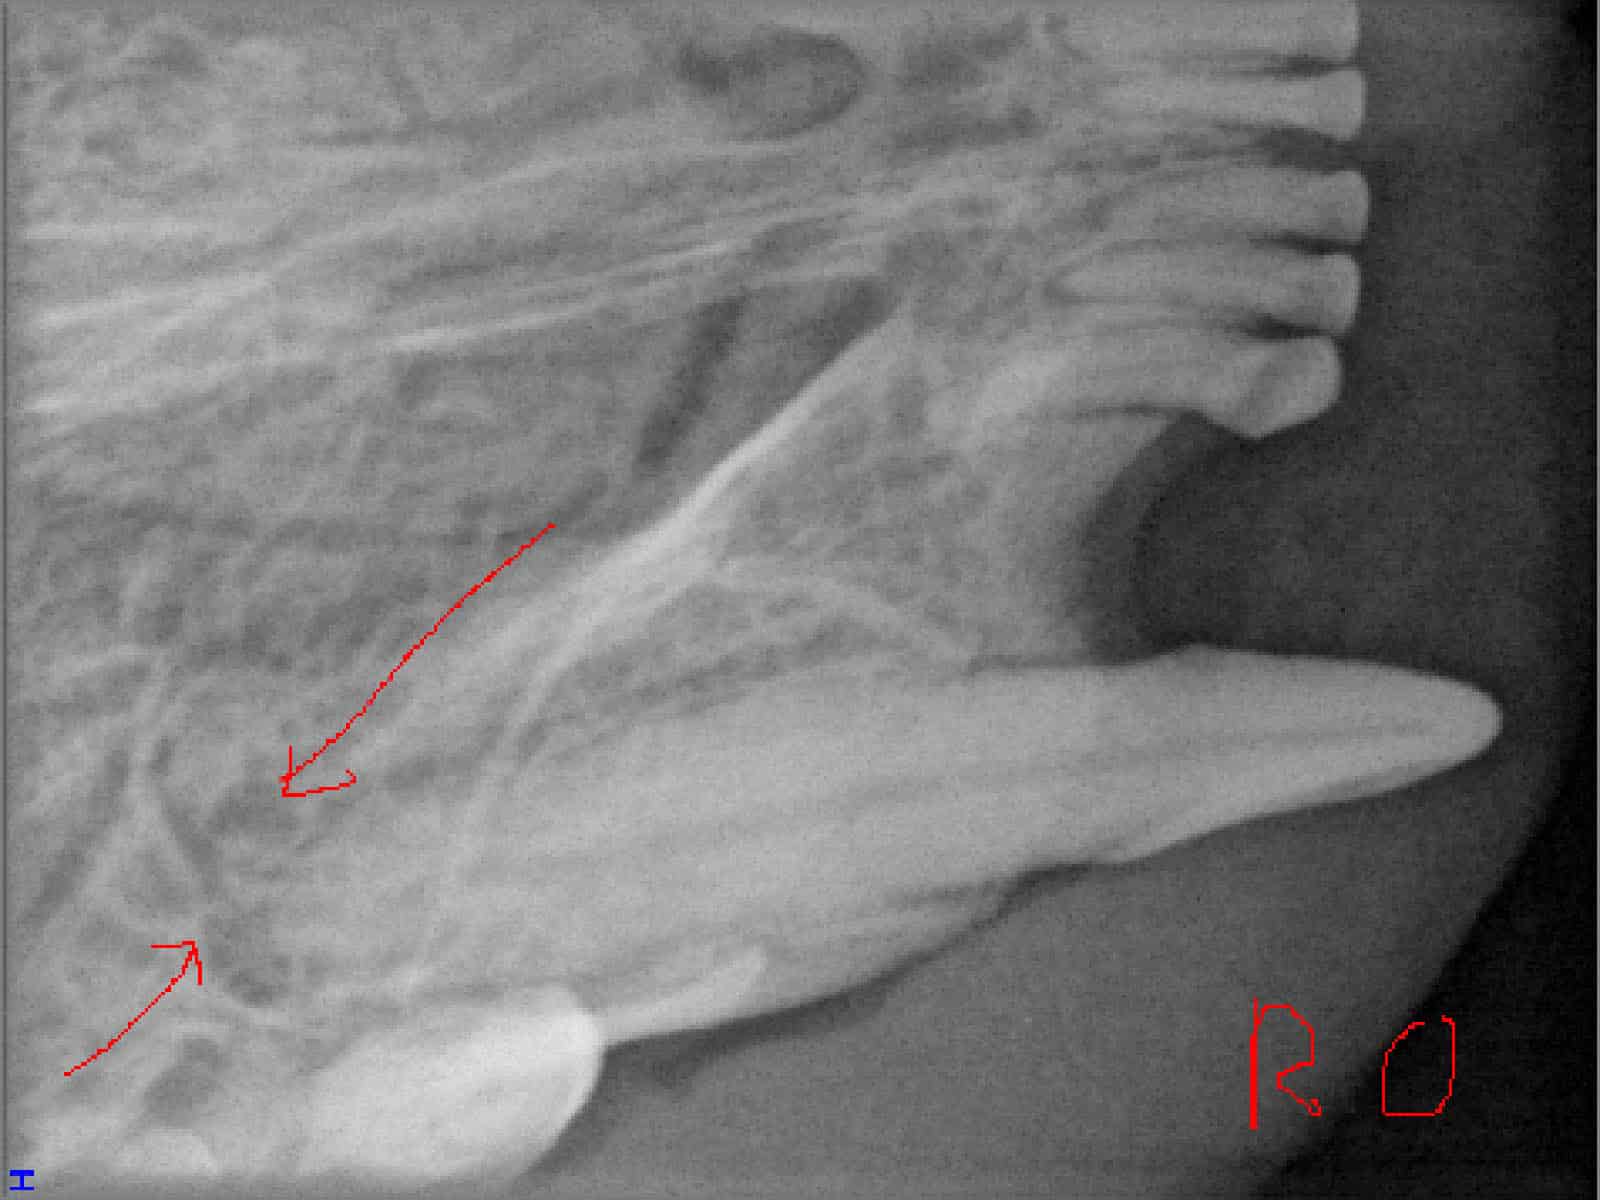

Das sehen Sie von außen – so sieht es auf den Röntgenbildern aus.

FORL Katze Röntgenbild

Röntgenbilder